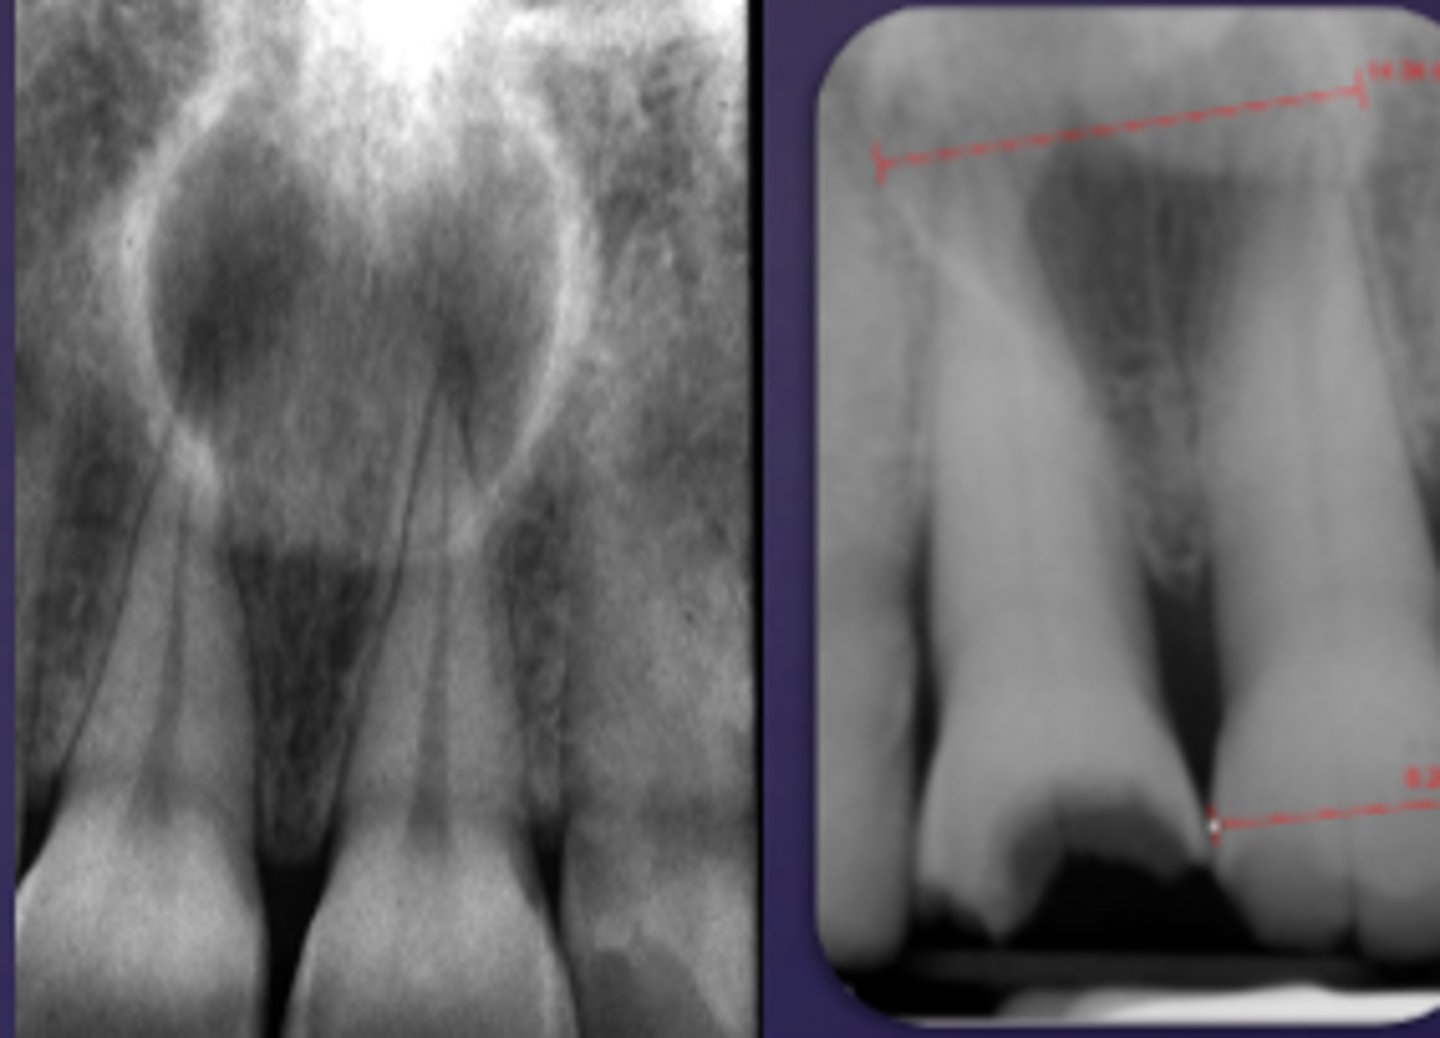

how would you describe this lesion?

A. well-defined, periapical radiolucent lesion associated with #24 and 25

B. ill-defined, periapical radiolucent lesion associated with #24 and 25

C. well- defined, multilocular periapical lesion associated with tooth number 24 and 25

D. mixed density, periapical lesion associated with teeth number 24 and 25

- Also note loss of apical lamina dura of 24, 25

What category would this lesion be part of?

Dysplasia

What would be a differential diagnosis for this lesion?

PCOD (stage 1)